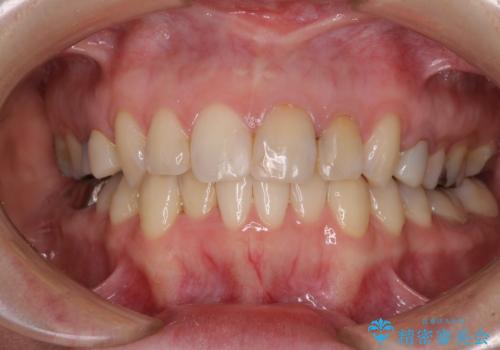

【モニター】前歯のデコボコと奥歯の虫歯 インビザライン治療と奥歯のセラミック治療

- 前歯のデコボコと奥歯の虫歯を気にして来院された患者様です。

主に下顎歯列全体の後方移動とIPR(歯と歯の間を削る)によってデコボコが解消するように設計し、インビザラインにより治療を行うこととしました。

矯正治療後半に下顎左右奥歯をセラミッククラウンにて補綴し、その後インビザラインによる歯列の仕上げを行うこととしました。

下顎前歯の叢生が速やかに改善されたため、1年3か月で治療を終えることができました。

下顎前歯は後戻りを起こしやすいため、舌側を細いワイヤーで固定することで後戻り対策を行っています。